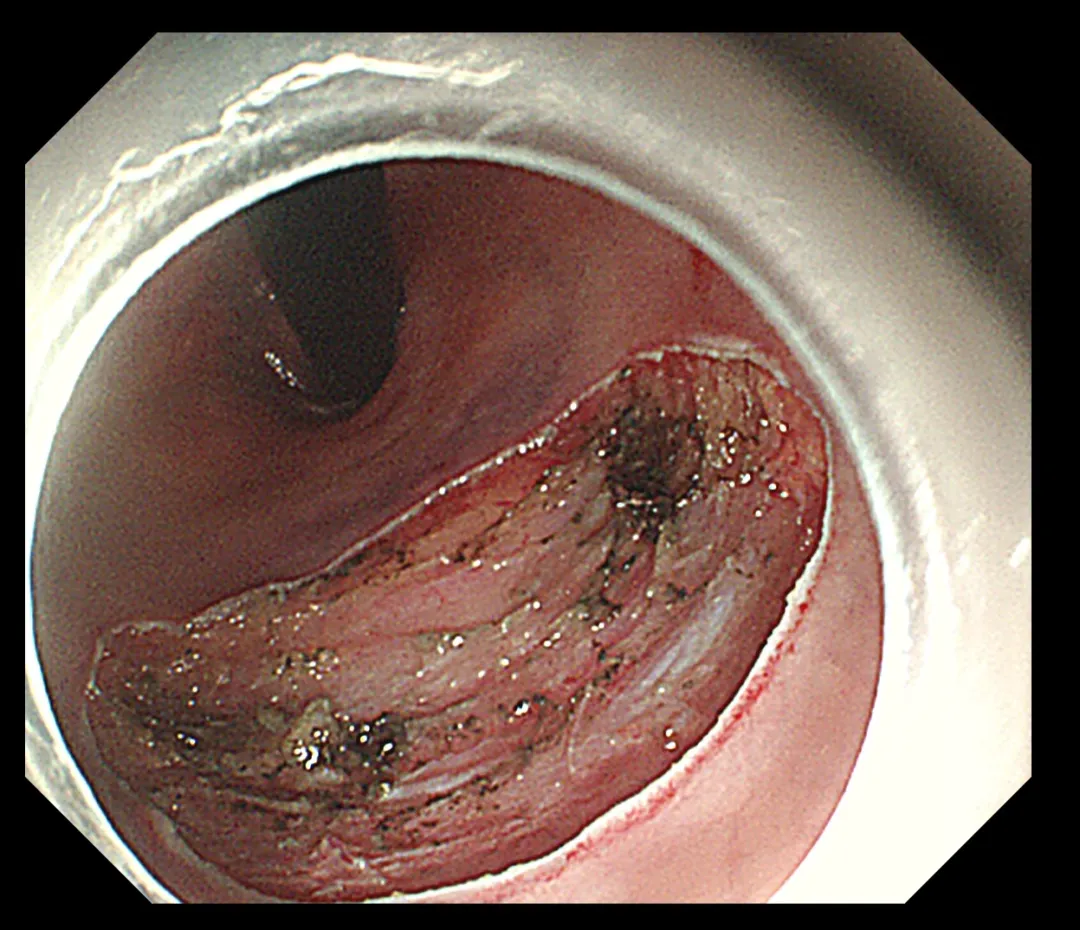

术中影像

手术过程中,内镜团队凭借精湛的技艺与细腻的操作,在方寸之间的肠腔内进行了“精雕细琢”。他们巧妙运用肠镜下黏膜剥离技术(ESD),将肿物从黏膜层完整剥离,既彻底根治了病变,又最大限度地保护了肛门的正常结构与功能。这一成果的实现,无疑为患者术后生活质量的提升奠定了坚实基础。术后,患者恢复状况良好,未出现任何并发症,现已顺利康复出院。